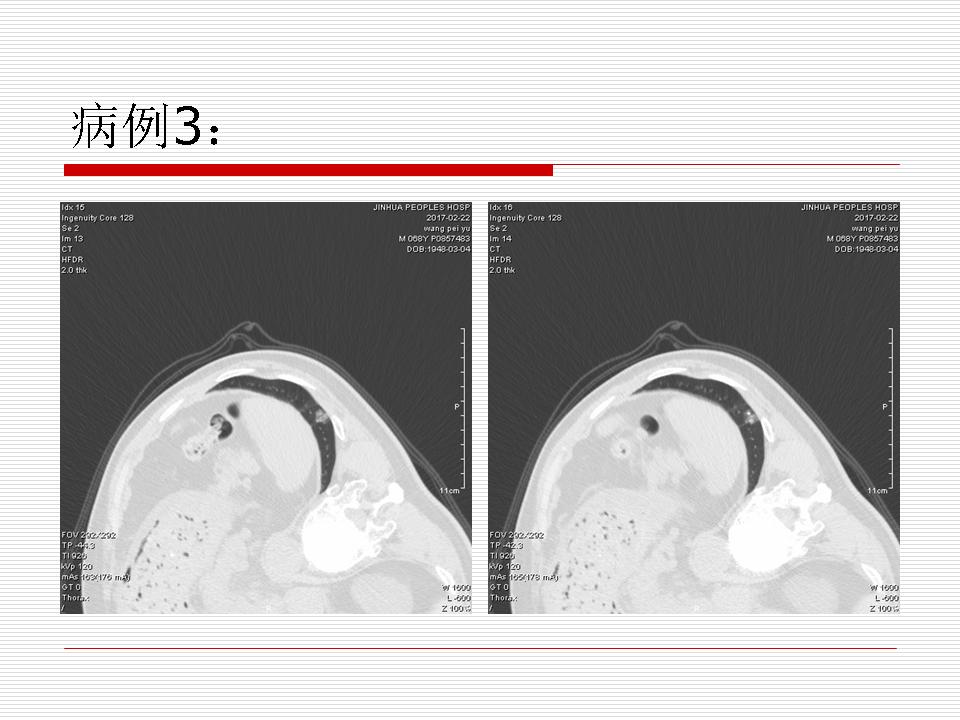

肺部阴影永恒且最重需要鉴别的是:到底是炎症还是肿瘤?但临床的病例中的影像表现难以界定或有些肿瘤特征,同时又有些炎症特点是非常常见的情况。作为临床医生我们怎么去总结分析,并找到之所以是炎症或之所以是肿瘤的细微差别或特点非常重要,也非常有用。2019.12.7浙江省2019年胸心外科学学术年会在宁波召开时,我的临床病例分析与经验总结<那些像肺癌的炎症与像炎症的肺癌>获得在大会交流的机会,以下为该PPT的内容,与你分享,希望对同道有益,有借鉴与启迪。若有探讨与进一不完善的建议,欢迎文末留言讨论: